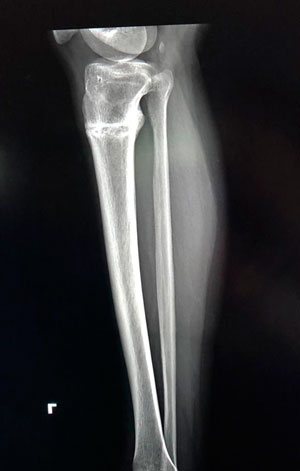

Дата операции - 12.07.2019г.

Дата снятия аппаратов - 17.10.2019г.

Срок сращения - 95 дней.